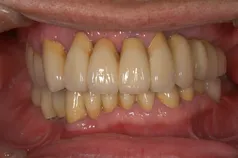

[症例1]

重度の歯周病で奥歯がすでになくなっており、そのため前歯もグラグラの状態でした。

右上の前歯(向かって左上)は自然に抜け落ちたそうです。

下の前歯の裏側には多量の歯石がたまっています。

【処置内容】

歯周初期治療、全体に歯周外科処置を実施、その後セラミックブリッジ、セラミッククラウン、

右上6・5番、左上3・4・5・6番、左下6番、右下4・6番にインプラントを実施。

• 治療期間:約2年

• 治療費:400万円

• 治療回数:30回